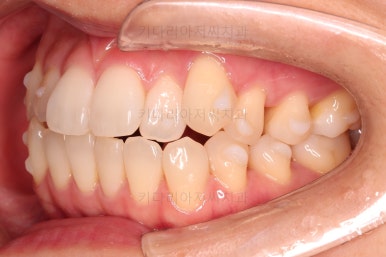

장치를 사용한지 1년 2개월째 사진입니다.

매우 가지런해졌죠.

보통 부산인비절라인은 풀세트로 3회가량 하게 되는데요.

이번 환자분은 1회로도 이 정도의 결과를 만들어 냈습니다.

이 정도의 느낌도 나쁘지는 않지만 미세하게 수정할 부분들이 보여 1회 더 제작하기로 했습니다.

두번째 세트를 진행 중입니다.

부족한 부분을 좀 더 맞춰주고요.

마무리를 하게 됩니다.